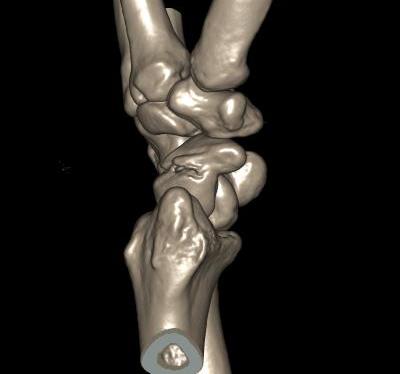

- perilunate trans-scaphoid dislocation

Scaphoid waist fracture 1 mm displaced

Scaphoid fracture with significant displacement

Scaphoid proximal pole fracture